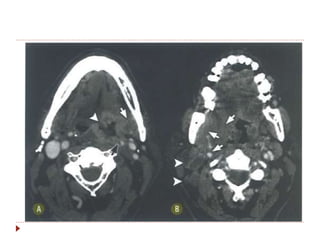

 Disseminação para linfonodos dos

níveis II, III, IV, V e retrofaríngeos.

Orofaringe  Mais agressivoque CEC de nasofaringe, com pior prognóstico.  Disseminação para linfonodos dos níveis II, III, IV, V e retrofaríngeos.  Sintomas: odinofagia, halitose, sangramento, perda de peso, linfonodo palpável.

Orofaringe - Linfoma Massa sólida em tonsilas palatinas e linguais.  Massas exofíticas com realce pós-contraste na fase venosa, na TC e na RM.  Principal diagnóstico diferencial é com hiperplaisia linfoide.  Linfonosos necróticos podem ajudar no diagnóstico, sugerindo neoplasia.